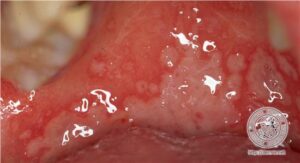

The extracutaneous manifestations are categorized as oral and/or genital aphthae; vasculo-, ocular-, entero-, or neuro-Behcet’s disease; renal disease; and arthritis. Oral apthosis recurring at least three times over a 12-month period is essential to the diagnosis (. In vasculo-Behcet’s disease, aneurysms and occlusive venous and arterial main vessel lesions occur. The ocular manifestations include uveitis, hypopyon iritis, optic neuritis, and choroiditis. Entero-Behcet’s disease manifests as diarrhea, constipation, abdominal pain, vomiting, and melena. Neuro-Behcet’s disease presents as brainstem dysfunction, meningoencephalitis, organic psychiatric symptoms, and mononeuritis multiplex . Asymptomatic microhematuria and/or proteinuria are among the renal manifestations. An oligoarthritis may involve the wrist, elbow, knee, or ankle joints. Morbidity and mortality in one large series of Turkish patients were greatest in young males; both the onset and the severity of ocular disease were greatest early in the course of disease, suggesting that the “disease burden” in Behcet’s disease is greatest early and that it tends to “burn out” over time .However, neurologic and major vessel disease can occur at any time and can have late onset 5 to 10 years into the course of illness . |

Extracutaneous lesions histologically mirror the skin changes. Oral aphthous ulcers demonstrate a central diffuse |

neutrophilic infiltrate with necrosis of the epithelium and connective tissue pathergy of the submucosa and peripherally a border showing dense lymphocytic infiltration with lymphocytic exocytosis and degenerative epithelial changes. Genital aphthae have the same appearance. The large-vessel arteriopathy represents an ischemic sequelum of a mononuclear cell vasculitis of the vasa vasorum (108), whereas venous thrombosis may be due in part to an underlying hypercoagulable state. A lymphocytic vascular reaction with or without mural and intraluminal fibrin deposition is the histopathology of neuro-, entero-, ocular-, and arthritic Behcet’s disease, with other organ changes such as demyelination and intestinal ulceration reflecting resultant ischemia (. The renal histopathology includes IgA nephropathy, focal and diffuse proliferative glomerulonephritis, and amyloidosis . |